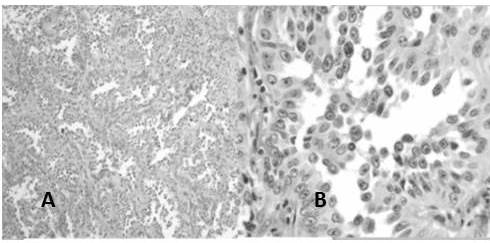

Por otro lado se reclasificaron 50 casos de carcinoma de CCE: encontrando que el CCE poco diferenciado no queratinizante representó el 40 % de los casos (Figura 11), el CCE bien diferenciado queratinizante resultó el 36 % (Figura 12), el CCE moderadamente diferenciado queratinizante representó el 20 % (Figura 13) y finalmente el CCE basaloide (Figura 14) fue el 4 % (Cuadro 7)

En el estudio los casos de carcinomas neuroendocrinos estuvieron representados en su mayoría por carcinomas neuroendocrinos de células pequeñas con 80 % de los casos (Figura 13), los carcinomas de células grandes (Figura 14) fueron 13,3 % y se observó un caso 6,7 % de tumor carcinoide típico (Figura 14) (Cuadro 10).